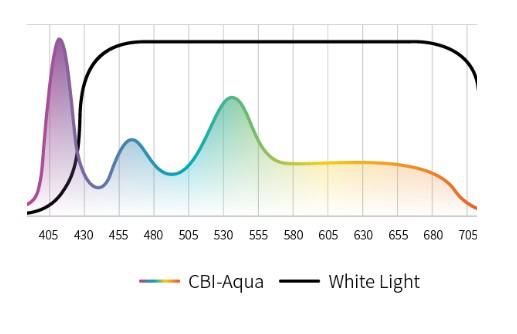

Три режима оптической хромоэндоскопии

Оснащен 4 светодиодными источниками света высокой яркости с независимым управлением, обеспечивающими многоспектральный режим окрашивания «белый свет + 3 спектра CBI». Спектральное окрашивание может повысить визуальный контраст между нормальной тканью и повреждениями, тем самым улучшая выявляемость небольших повреждений. Технология оптического окрашивания (CBI) – удобный и эффективный инструмент для выявления раннего рака, опухолевых и воспалительных процессов.

CBI regular позволяет легко выявлять поражения слизистой оболочки и подчеркивать распределение подслизистых сосудов. |  |

CBI indigo Усиливает контраст между слизистой оболочкой и кровеносными сосудами. |  |

CBI aqua способствует лучшей визуализации структуры слизистой оболочки. |  |

Три режима оптической хромоэндоскопии (CBI). Многоспектральная визуализация с 4 светодиодами высокой яркости:

- CBI regular — визуализация слизистой и подслизистых сосудов.

- CBI indigo — усиление контраста между слизистой и сосудистой сетью.

- CBI aqua — улучшенное отображение структуры слизистой.